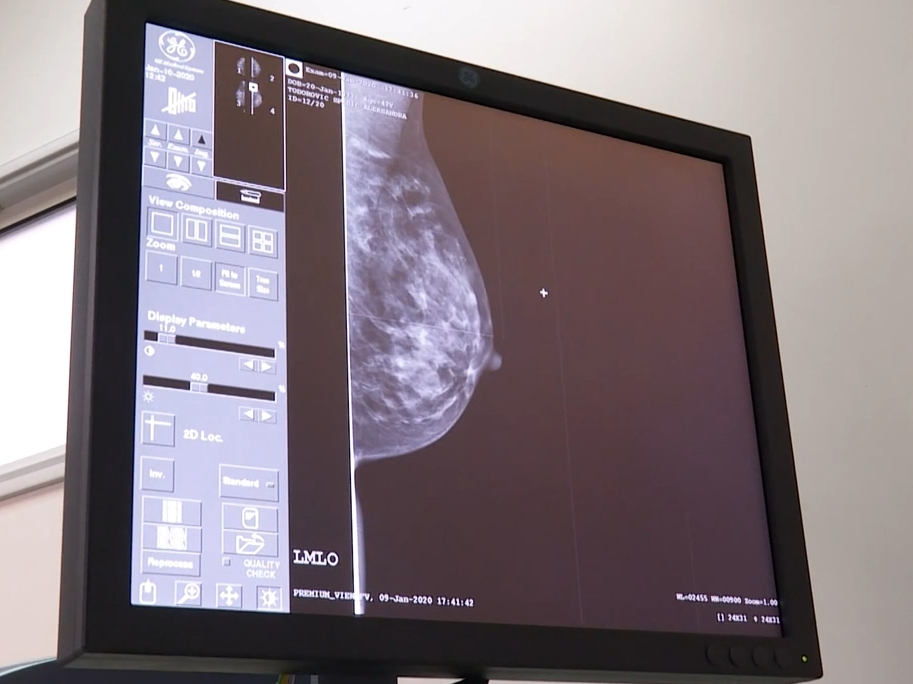

Imaćemo dovoljno aparata, pacijenti neće morati nigde da idu da se snimaju, naglasila je Grujičić i dodala da će zbog renoviranja zgrade i postavljanja opreme pacijenti morati do avgusta da se strpe za snimanje, dok će mamografija raditi sve vreme.